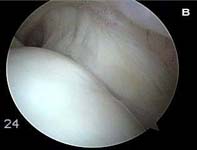

The video below is a diagnostic arthroscopy procedure as viewed from the back of the joint looking to the front. This patient has mild, partial thickness fraying at the rotator cuff insertion. This tear is analogous to the tear show in Fig. 5.

- partial-thickness or incomplete tears can occur. While these tears may progress to complete tears, rehabilitation can frequently strengthen the remaining intact cuff tissue and halt the process. Many persons with partial-thickness tears will never require surgery if they undergo an appropriate physical therapy rehabilitation to address muscle imbalances. (See Fig. 5. and video above)